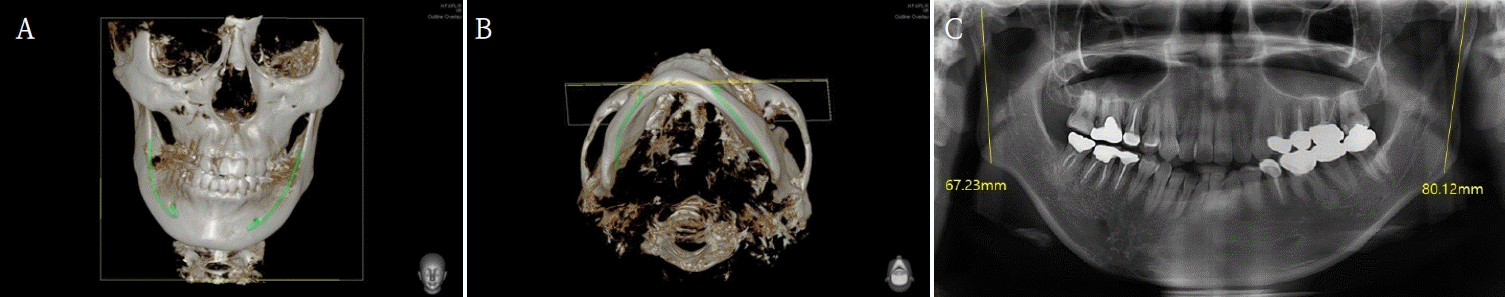

32세 여성이 우측 턱관절의 통증과 개구제한을 주소로 내원하였다. 내원 전에 3차례에 걸쳐 각각 다른 의료기관에서 턱교정수술을 받은 경험이 있고, 음식물 저작이 힘들고 입이 비뚤어져 사회관계에도 문제가 있었다. 안모는 좌측으로 변위된 비대칭이 관찰되었고 교합은 상악골의 우측 변위, 하악골의 경사진 좌측 변위로 인해 치아 중심선 비대칭을 포함하여 전치부의 개방교합과 구치부의 반대교합이 관찰되었다(Fig. 5). 우측 관절부위 통증과 다수의 수술로 인한 저작근 주위 조직의 경직으로 인해 자발적 최대개구량은 23mm이었다. 파노라마방사선영상에서 우측 하악과두가 좌측에 비해 glenoid fossa으로 부터 떨어져 있고 전방으로 기울어져 있는 것을 관찰할 수 있었다(Fig. 6). 이전 하악골편 고정시 하악과두가 포함된 근심골편이 후방으로 위치하여 고정된 것과 상악골의 우측 변위되어 고정된 것을 개선시키기 위해 4번째 턱교정재수술(4th reoperation)과 치아교정술을 계획하였다. 상악골의 수술 시 하악골의 안정을 위해 후상방이동 2.5mm와 기울어진 교합평면의 개선을 위해 교합평면 수정1.5mm를 하였으며 동시에 상악의 비대칭 개선을 위해 좌측으로 1.5mm 측방이동하였다. 하악골은 기존의 골절선을 이용하여 골편을 분리한 후 변위된 우측 근심골편을 관절와에 재위치시키고 상악골의 위치에 따라 고정하였다. 수술 중 비대칭이 해소된 것과 개구량 45mm 확보된 것을 확인하였다. 수술 후 파노라마방사선영상과 3D CT영상에서 치아의 정중선이 일치하고 전치부 및 구치부의 반대교합이 해소된 것을 볼 수 있었다. 그리고 우측 하악과두가 관절강 내 재위치된 것과 하악지의 방향이 좌, 우측 비슷하다는 것을 확인할 수 있었다(Figs. 7 and 8). 수술 후 2주부터 개구연습과 치아 교정을 진행하였으며, 수술 후 3개월에 자발적 개구량 35mm 확인하였다. 다수의 수술로 인한 구강내 반흔 조직과 저작근 주위의 경결감으로 인해 적극적인 개구훈련을 하였으며 수술 후 6개월에 38mm의 개구량을 보였으나 통증은 없고 일상식이 가능하여 이후의 경과관찰에는 내원하지 않았다.- 증례 3

턱관절을 포함한 저작 부위의 비정상적 하중은 안면부 통증을 비롯하여 턱관절증, 관절염과 같은 턱관절 질환과 치아 파절, 보철물 및 치과 임플란트의 파절 등 여러 가지 문제를 야기할 수 있다. 이러한 턱관절 질환에 대해 몇 가지 가능한 원인이 제안되었지만 조절되지 않은 힘과 안면비대칭이나 부정교합과 같은 턱뼈의 구조적 문제는 관절의 생체 역학 변화에 기여하는 가장 흔한 병인학적 요인으로 생각할 수 있다[11]. 첫 번째 환자의 경우, 좌측 하악지가 우측에 비해 12.89mm 길었고 이 영향으로 하악골의 중심은 우측으로 편위되어 있었다. 이러한 경우, 대부분 짧은 쪽으로 하중이 많이 전달되어 턱관절 질환이 발생할 가능성이 높다. 이 환자는 상대적으로 짧은 하악지를 가진 우측에 관절 잡음을 동반하여 간헐적 과두 걸림이 있었다. 턱관절에 가해지는 과한 하중은 턱관절 원판이 전방 변위되고 원판 후방조직에 힘이 가해져 통증과 관절 잡음을 포함한 턱관절증을 일으킨다[20]. 하지만 비대칭이 크게 존재하는 경우, 반드시 이환측에만 턱관절 장애가 존재하는 것은 아닌데, 이것은 통증이나 불편감을 해소하기 위해 반대측으로 비틀어 저작한다던지 편측 저작을 한 결과일 것이다. 이런 현상은 첫 번째 환자와 반대의 비대칭을 가진 환자의 경우에서 관찰할 수 있었는데, 좌측으로 편위된 비대칭이 있었으나 반대측에 턱관절증이 있었던 경우이다(Fig. 11). 하악골의 열성장과 제2급 부정교합의 경우 정상교합에 비해 상대적으로 짧은 하악지와 하악과두로 인해 턱관절의 디스크 전위나 골관절염이 생기는 취약한 환경에 있는 것과 유사하게 비대칭 하악골에서 구조적으로 하중을 해소하는데 불리한 구조이다[16-19]. 이런 골격적 문제를 해결하기 위해서는 턱교정수술과 치아 교정이 필요할 수 있다. 턱교정수술에서 고려해야할 점은 틀어진 교합평면의 수정, 하악지의 관절에서 내려오는 방향과 측방으로 벗어나려는 힘의 조절 등이다. 상악골의 재위치 시 수술 후 비대칭을 해소하기 위한 하악의 위치를 고려하여 rotation, canting correction, shifting 등 3차원적으로 수술계획을 하여야한다. 그리고 하악골의 시상분할절골술 후 고정 시, 하악과두를 포함한 근심 골편이 관절내에서 앞뒤, 좌우 등으로 치우치는 힘으로부터 자유롭게 해야 하는데(freeing) 이 때는 근심골편과 원심골편 사이에 저항이 없도록 고정시켜야 한다. 상악골과 하악골이 정중선에 재위치되어도 하악골체의 부피 차이와 턱끝 부위의 모양 차이로 인한 안면비대칭은 하악골의 골체변연성형술과 턱끝 수술을 통해 상당부분 해소해줄 수 있다. 하악골의 시상분할절골술 이후 근심골편을 고정할 때 관절부의 위치를 잘못 설정하면 두 번째 환자의 경우처럼 수술 이후에 개구제한이 있고 해당부위의 턱관절에 통증이 있을 수 있다. 해당 환자는 좌측 하악과두가 glenoid fossa에서 전방으로 떨어져 위치되었는데 이것은 근심골편의 고정시 후방으로 밀려 고정된 결과 일 수 있다. 후방압력에 의해 원심 골편은 좌측으로 틀어지며 치아는 편측으로 비틀어져 전치부 개방교합과 구치부의 반대교합이 나타났으리라 추측된다. 이러한 이유로 관절의 원판은 전방변위되고 후방조직의 압력으로 통증을 느끼게 되는데, 교합력이 가해지면 과도한 힘이 아니더라도 구조적으로 통증과 턱관절증을 일으킬 수 있을 것이다. 또한 잘못 고정된 하악지의 경우, 관절에 전해지는 힘의 방향이 좌우 다를 수 있다. 첫 번째 사례와 같이 하악지의 길이가 양쪽이 다른 경우, 관절에 전달되는 힘이 짧은 측을 축으로 하중의 차이가 있어 이환된 쪽에 턱관절 질환이 발생할 수 있는 것을 살펴보았다. 이와 비슷하게 관절로부터 하악각으로의 방향이 서로 다른 경우, 하중 전달량의 차이로 턱관절질환이 생길 수 있다. 따라서 두 번째 사례에서처럼 하악지의 고정 시 양측의 각도를 비슷하게 설정해주는 것이 이후 턱관절에 양호한 하중 전달 구조에 유리하다(Fig. 7). 수술 이후 개구연습을 통하여 정상 범위의 개구량을 회복함에 있어 두 번째 사례에서는 고려해야할 점들이 있었다. 이전의 3번에 걸친 턱교정수술로 인해 잔존하는 근심골편의 양이 적었고 이로 인해 개구연습 시 과도한 힘에 의한 뒤틀림을 조심해야 했다. 그리고 골막과 저작근 주위의 반흔조직성 경결감으로 온열을 동반한 물리치료를 통해 저작근의 활성화 범위를 점차 넓혀갔다. 수술 전 상악골의 우측 편위로 인해 더욱 좌측으로 틀어져 보이던 하악을 보상성 개구활동으로 중심선을 맞추려고 했던 습관을 교정하기 위한 행동요법도 시행하였다. 행동요법은 습관의 교정으로 질병을 치료하는 방법이며 이중 바이오피드백은 자발적으로 제어할 수 없는 생리 활동을 공학적으로 측정하여 지각 가능한 정보로 생체에 전달하고, 그것을 바탕으로 학습, 훈련을 되풀이하여 자기 제어를 달성하는 기법이라 알려져 있다[21]. 턱관절 질환의 분야에서 바이오피드백은 수면 이갈이를 조절하는데 좋은 역할을 한다고 보고되어진다[22,23]. 세 번째 환자의 경우, 턱관절 부위의 통증과 심한 이갈이로 인해 치과의원에서 스플린트 치료, 보톡스 치료, 물리치료 등 수년간의 치료를 받았지만 나아지지 않아 바이오피드백을 통한 수면 이갈이를 관리하고자 하였다. 통증은 주로 측두부에서 있었으며, 수면 중 발생된 저작근의 과긴장으로 아침에 기상 후 두통이 심하였다. 과긴장되는 근육의 활동을 줄이기 위해 보톡스 주사가 주로 사용되는데 교근에만 주사하는 경우, 측두근의 활동이 강해져서 오히려 측두부에 통증을 호소하기 한다. 이 환자의 경우에도 이전 주사 부위가 아래쪽에 국한되어 있었다는 점은 교근의 위축이 오히려 측두근의 근육통을 발생시키지 않았나하는 추측을 해볼 수 있다. 보톡스 주사는 3개월 간의 효과를 가지고 있어서 그 이후에 관리가 되지 않으면 다시 저작근의 과긴장에 의한 턱관절 질환을 재발시킬 수 있다. 스플린트는 제작 후 사용하다가 수면에 방해가 되고 불편하다는 이유로 적극적인 사용이 힘들었다고 하였으며, 실제로 스플린트 자체가 수면 이갈이를 방지하기 보다는 치아를 보호하고 턱관절 부위에 간격에 의한 안정을 주기에 비기능적 저작활동을 차단하는데는 한계가 있다. 사용된 바이오피드백 장치는 수면 중 측두근의 활동을 근전도를 이용하여 실시간으로 측정하고, 일정 역치 이상의 과긴장이 감지되면 생체에 진동 자극을 주어 clenching이나 grinding을 억제하도록 설계되어 있다. 본 연구에서는 이러한 기능을 갖춘 상용화된 장치인 Goodeeps(Miraclare, Republic of Korea) [24]를 사용하였다. 사용 시작 후 3일까지 장치를 통해 이갈이가 있을 때 근전도에서 확인이 되었으나 부착 부위의 이물감과 진동의 세기 조정 단계의 불편감 등으로 수면 중 잠을 깨는 경우가 있었다. 이 기간 동안 유의미한 이갈이(4초 이상)는 4에서 13회 정도 있었고, 다음날 아침에 일어났을 때 불편감이 점점 감소하는 기분이 들었다고 한다. 5일차 부터는 장치를 사용하는데 크게 불편한 점이 없었고 사용 후 3주차에서부터 진동이 필요할 정도의 이갈이는 발생하지 않았다. 진동을 주어도 이갈이가 계속되면 주어지는 진동의 크기를 높여 이갈이가 멈출 때까지 진행되기도 하였다(Fig. 12). 비기능적 행동을 할 때 생체내로 신호를 주어 제어하는 방식의 바이오피드백은 수면 이갈이의 발생시 진동을 주어 근 활동을 멈추게 하고 이것이 반복되면 무의식 중에 학습이 되어 이후 비기능적 습관을 회피하지 않을까라고 추측해 볼 수 있다. 실제로 환자는 6주 이후 바이오피드백 장치를 사용하지 않은 상태에서도 저작근에 힘을 주는 것에 대한 인지와 경계를 하여 이전의 턱관절 질환이 줄었다고 하였으나, 이에 대한 근거자료가 부족하여 이후 연구가 필요하다고 생각된다.턱관절 질환이 있는 환자를 문진할 때 다수의 경우에서 본인의 과도한 저작력을 인지하지 못한다. 그들은 수면 중 이를 가는 것이 없다고 하고 평소에 지그시 깨물고 있는 습관이 있는지 알지 못한다. 또한 턱관절 질환이 있는 상태에서는 딱딱하거나 질긴 음식을 제대로 씹지 못하여 턱에 힘을 주지 않는데도 계속 아프다고 하는 경우도 있다. 이것은 환자가 수면 중에 clenching과 grinding을 하거나 이것의 연장으로 낮에도 무의식적으로 깨물고 있을 가능성이 높다. 이러한 경우, 바이오피드백 장치는 환자와 의사에게 근전도 데이터를 이용한 정확한 저작근의 활동을 제공하여 턱관절 치료의 진단에 도움을 줄 수 있고, 의료기관에서뿐만 아니라 실생활 환경에서 비기능적인 저작력을 측정할 수 있고 유해한 행동에 대해서 조절할 수 있기에 턱관절 질환의 행동치료에 있어서 큰 역할을 할 수 있다고 본다. 턱관절 부위에 계속되는 부하는 저작근의 통증과 관절의 내장증, 그리고 골관절염 등을 유발하고 치료 이후에도 재발하게 하는 주요 요인으로 작용하기 때문에 힘의 비대칭성과 비정상적 강도 및 빈도를 조절하는 것이 턱관절 질환 치료의 시작이라고 볼 수 있다. 특히 행동요법 중 하나인 바이오피드백 장치는 습관성 질환인 턱관절 질환의 진단 및 관리에 도움을 줄 수 있다.